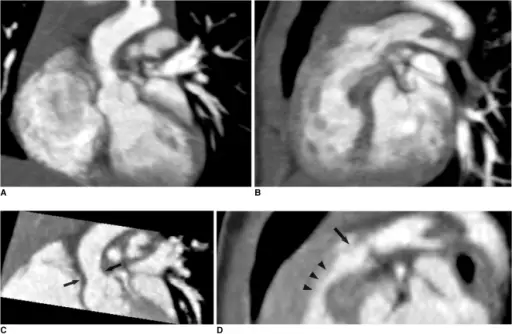

Ventricular Septal Defect (VSD)

A ventricular septal defect is a flaw in the wall that separates the right and left ventricles, or septum.

Ventricular septal defect is the most common congenital cardiac condition.

Ventricular septal defect is inextricably linked to fetal alcohol syndrome.

Ventricular septal defect results in a shunt from left to right.

Age at presentation and defect size both depend on the ventricular septal defect size.

Large ventricular septal defect can cause Eisenmenger syndrome.

Treatment of large ventricular septal defect involves surgery.

Small ventricular septal defects are frequently asymptomatic.

Small flaws might naturally close.